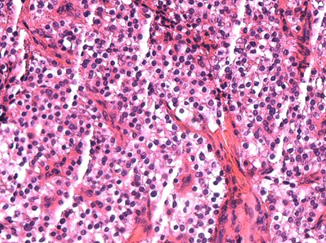

Histopathological examination of parathyroid adenocarcinoma (Courtesy Dr. V. Penopoulos)